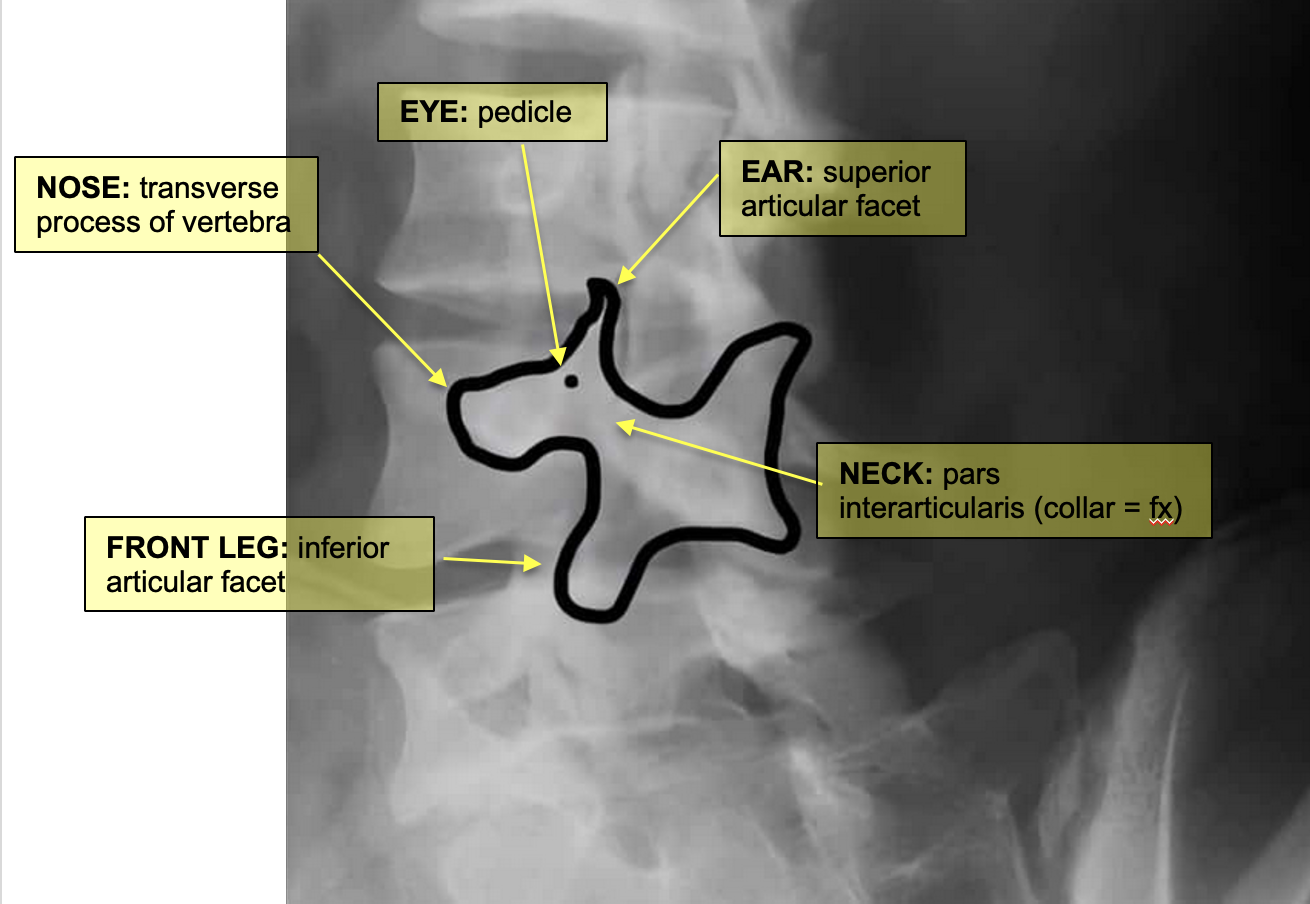

approach to lumbar xrays

ABCCP

Alignment

follow corners of vertebrae from one level to the next

Bones

Cortical outline, VB height, integrity of pedicles & transverse pro.

Cartilage

IVD grad

Increase in height from sup-inf. L5/S1 narrower

Coverage

ensure entire lumbar spine is visible in each scan

Posterior Elements

check elements (Pedicles, lamina and Pars inter

Articularis)

A 17 year old elite gymnast presents to her GP with a 5-month history of lower back pain, which increases in intensity upon hyperextension.

Lateral lumbar-spine x-ray reveals translation of a vertebral body due to a bilateral pars interarticularis fracture.

Which vertebral body and which columns are abnormal?

radiolucent fracture is seen at the pars interarticularis (facet joint) of L4 and L5, causing anterior dislocation (spondylolisthesis) of the vertebral body (L5 in this case)

Middle column: posterior shift at the L5 vertebral level

This would also stretch/displace the anterior longitudinal ligament due to posterior translation in the anterior column

pars interarticularis fracture

pars interarticularis (pars) lies between the superior and inferior articular process at each zygapophyseal/facet joint

usually L5 level

bilateral: spondylolisthesis

unilateral: spondylolysis

spondylolisthesis

bilateral pars interarticularis fracture at the L4/L5 level

disc has slipped posteriorly

stretches/displaces the anterior longitudinal ligament due to posterior translation in the anterior column

spondylolysis

unilateral pars interarticularis fracture

disc has not moved